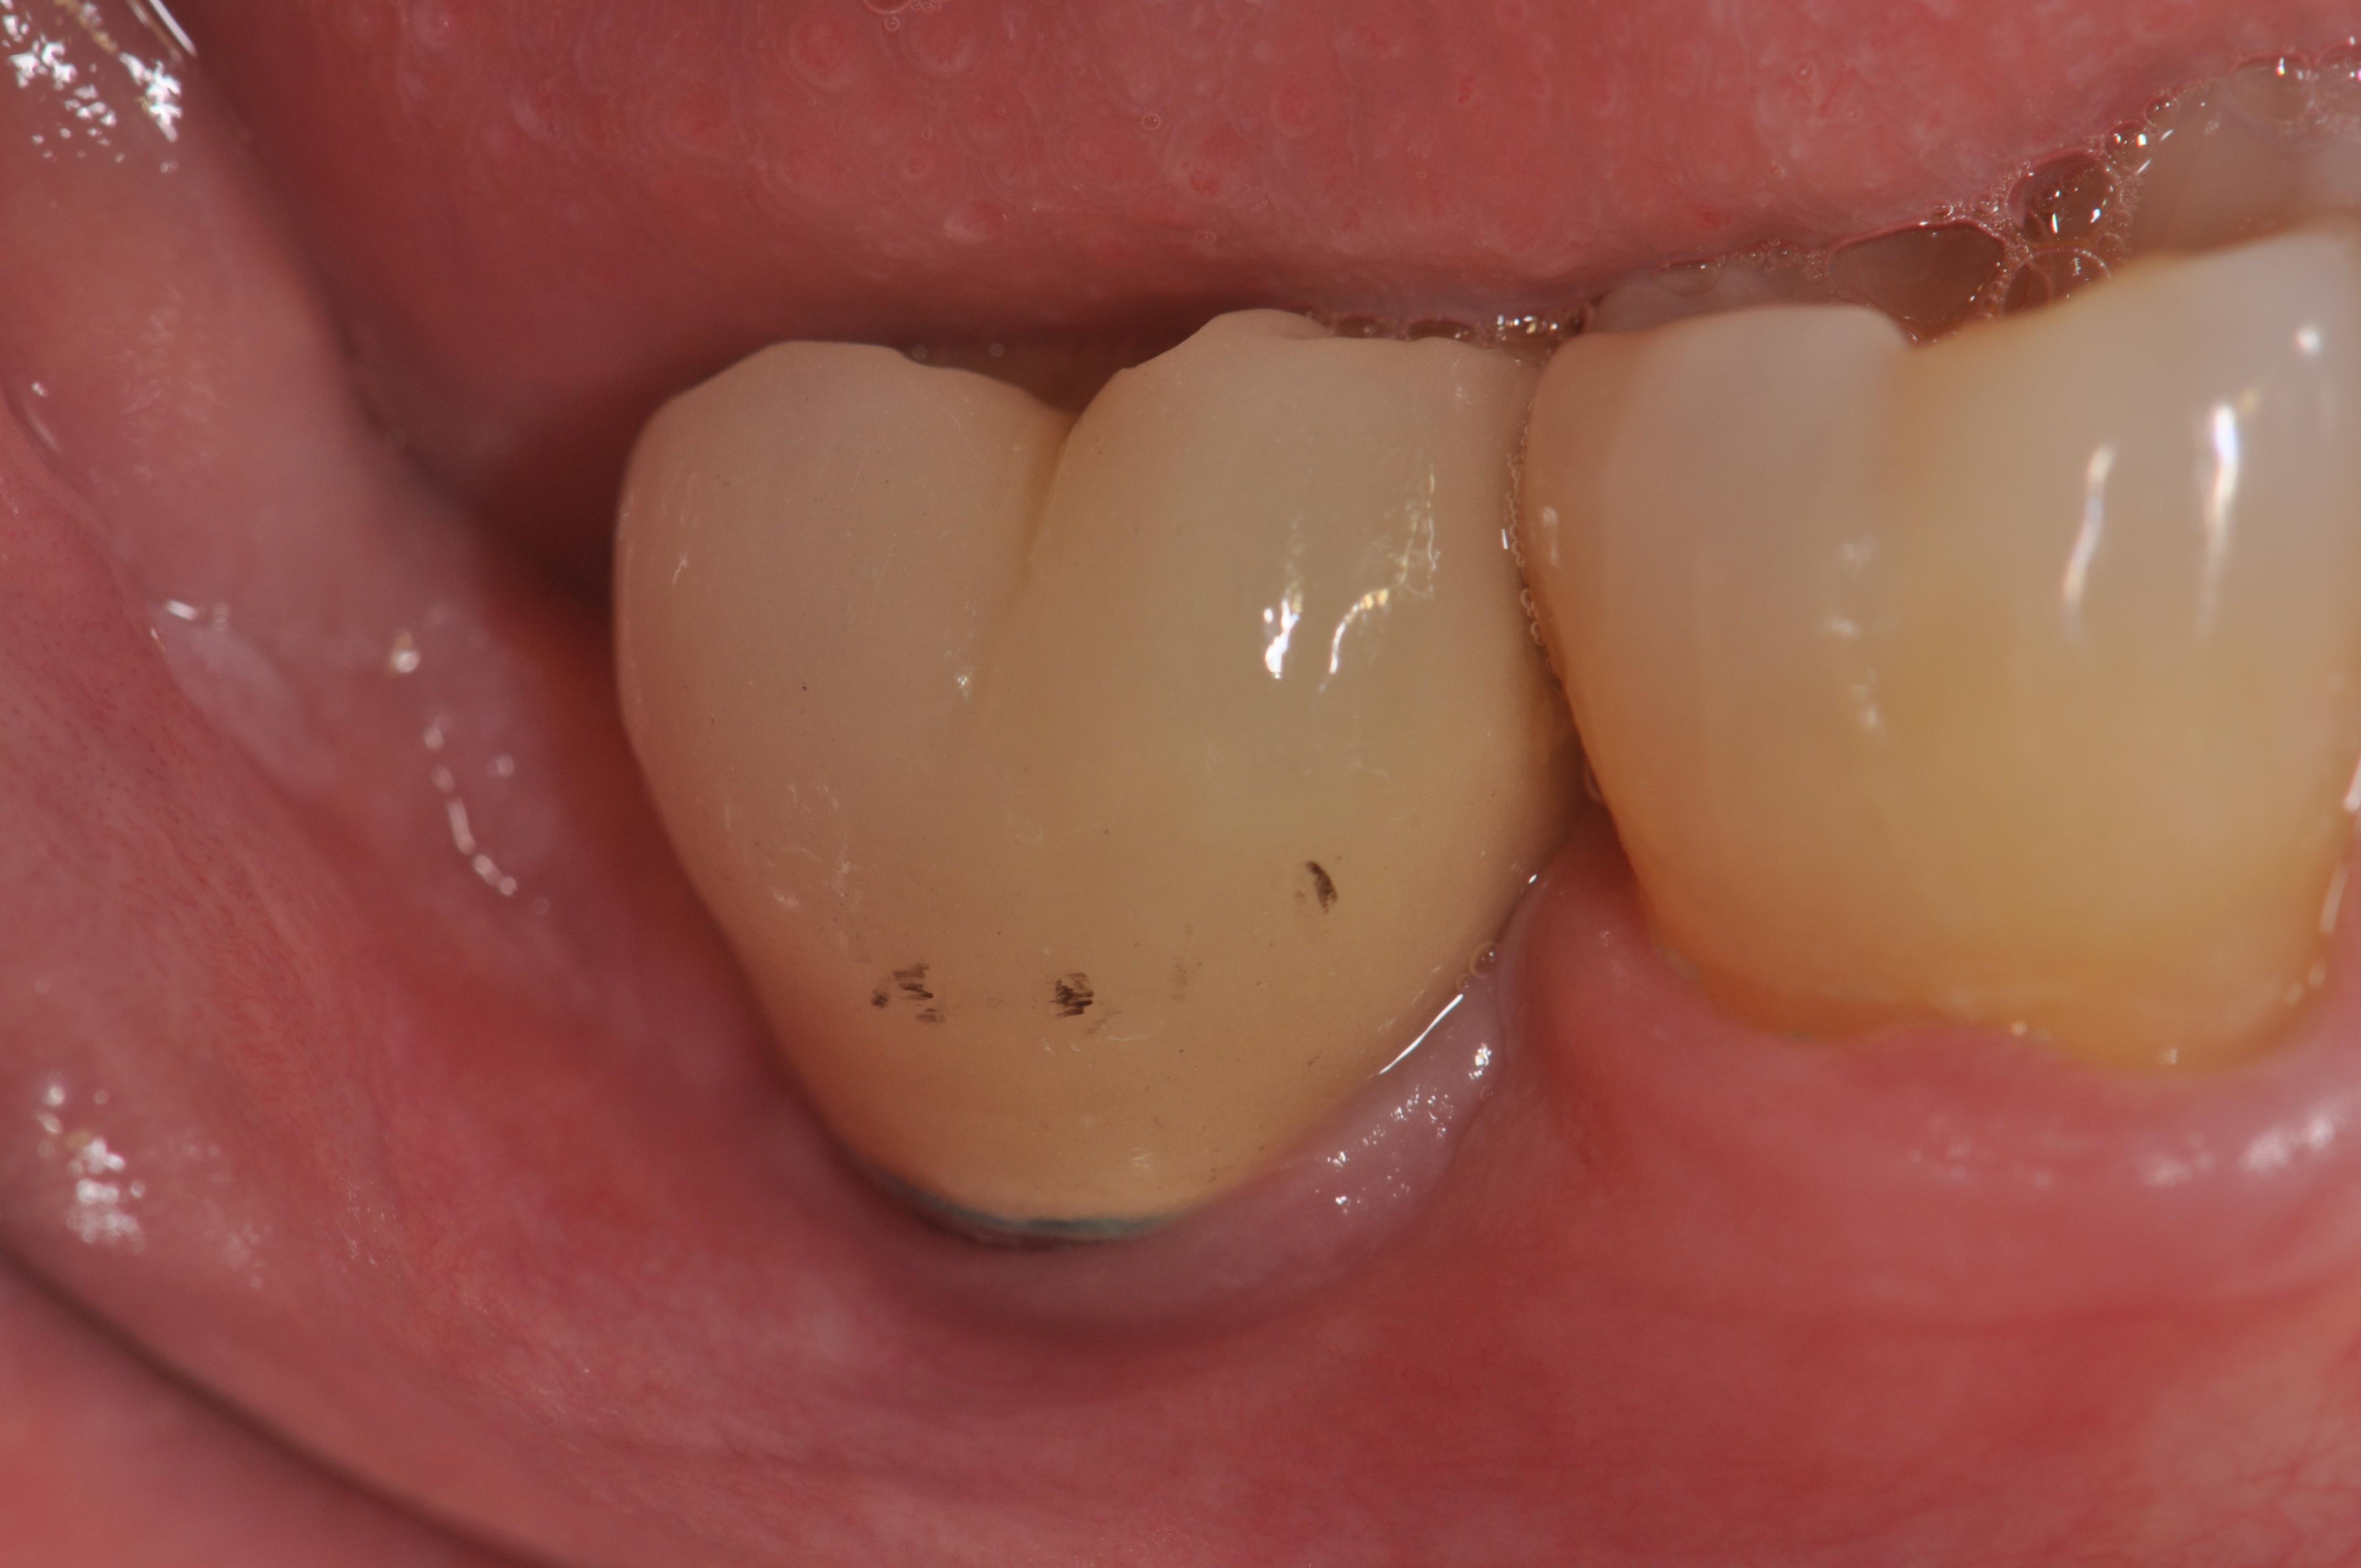

Figure 4

The flaps have been sutured together using expanded polytetrafluoroethylene.

Figure 5